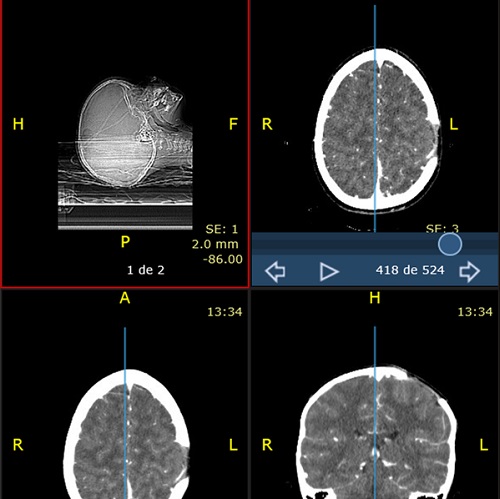

Paciente de 4 años que acude con su madre a consulta por bultoma en cuero cabelludo descubierto de forma casual 7 días antes, sin relación con antecedente traumático y con dolor a la palpación. Desde entonces presenta despertares nocturnos con irritabilidad, que mejoran con analgésicos. Antecedentes familiares y personales sin interés. Desarrollo madurativo normal. Vacunas adecuadas para su edad. No alergias conocidas. El paciente presenta muy buen estado general, apirético y con exploración normal, tanto somática como neurológica, salvo tumoración de consistencia blanda en región parietal izquierda de 2,5-3 cm de diámetro, dolorosa a la palpación. Se deriva al hospital de referencia para pruebas de imagen. La Rx de cráneo muestra una lesión osteolítica en sacabocados, posiblemente compatible con GE (Figura 1). Rx de tórax, serie ósea y ecografía abdominal normales. TAC craneal evidencia los mismos signos (Figura 2). La RMN detecta una lesión única intraósea expansiva parietal izquierda, que atraviesa la tabla ósea externa e interna con mínimo engrosamiento, e hipercaptación de la duramadre subyacente, sugerente de GE como primera posibilidad radiológica. Hemograma y bioquímica dentro de la normalidad.

Figura 2. Tomografía axial computarizada craneal sin contraste

El paciente permanece asintomático hasta un mes después, cuando se objetiva un nuevo bultoma doloroso al tacto, medial a la lesión previa, realizándose nuevo TAC cerebral y confirmándose una lesión lítica de nueva aparición en la región parietal parasagital izquierda, medial a la lesión anterior, sin componente de partes blandas (Figura 3).

Figura 3. Tomografía axial computarizada cerebral con contraste